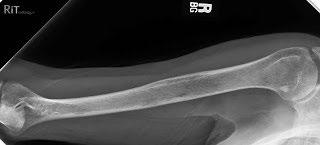

Imaging:

– Skeletal survey: Series of X-rays; less sensitive than other techniques

– Whole body low dose (CTWB-LD CT )

– Positron Emission Tomography (PET/CT)

– Magnetic Resonance Imaging (MRI)

Healthy bone versus myeloma bone disease